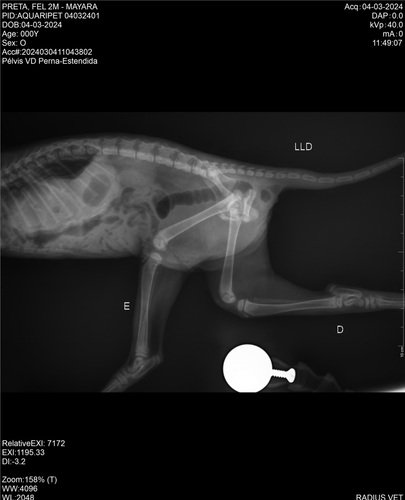

Oi pessoal, espero que estejam bem. Domingo a noite quando voltava para casa vi um motociclista atropelar essa bebezinha, ele não prestou socorro e eu não poderia deixar ela lá desse jeito. Levei ela ao veterinário e preciso de ajuda! Ela está com diversas fraturas graves, luxação no joelho, fratura acetabular e hérnia diafragmática - tudo devido ao impacto do atropelamento. Se você puder auxiliar com qualquer valor na vaquinha online ou entre em contato comigo para mais informações. Após ela se recuperar, também precisaremos achar um lar, pois eu não consigo ter mais 1 gatinho. Agradeço muito a atenção e se o seu coração for tocado e for possível ajudar essa pequena, agradecemos imensamente. Um lar com gatinhos é um lar com mais amor 🥰 segue imagens da gatinha e exames, bem como valor da clínica Aquaripet até o momento